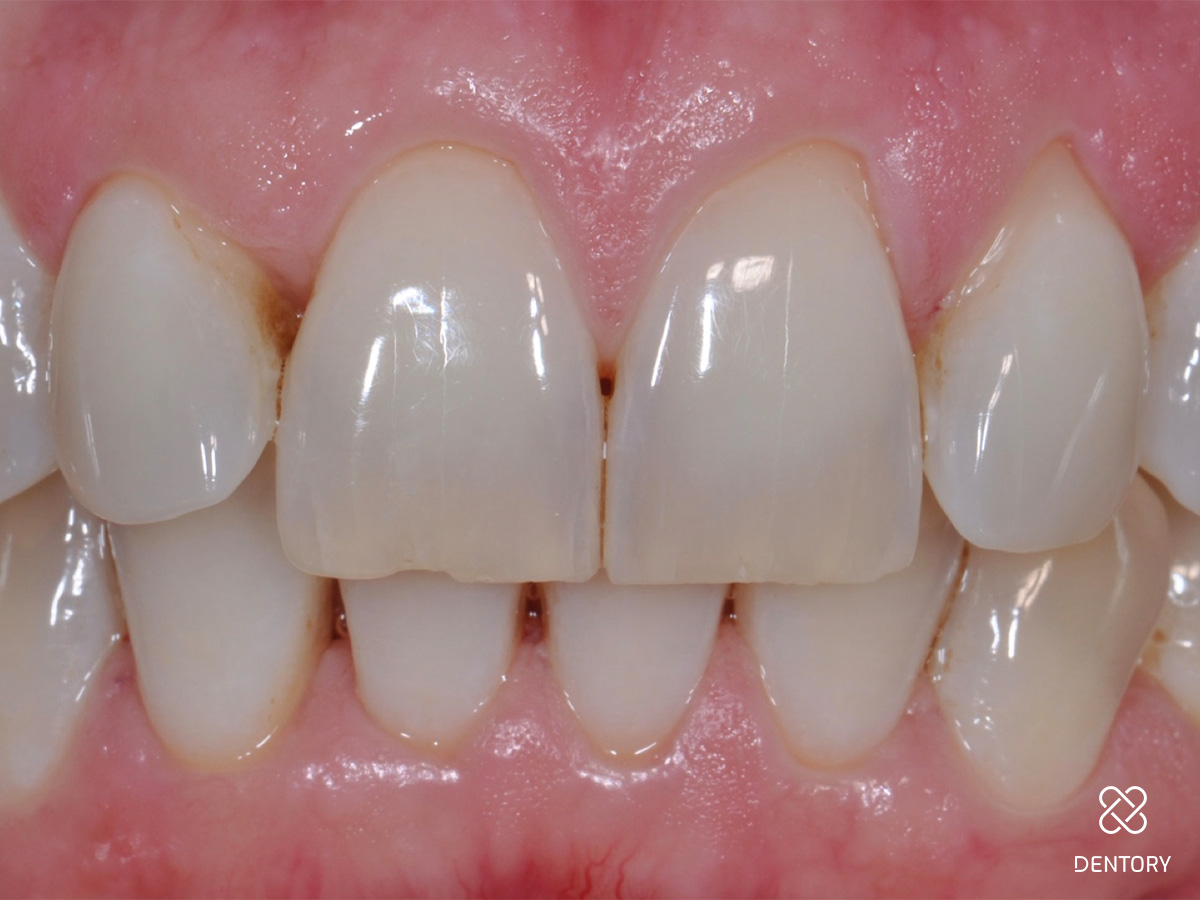

Abbildung 1

Ausgangssituation: Frontalansicht.